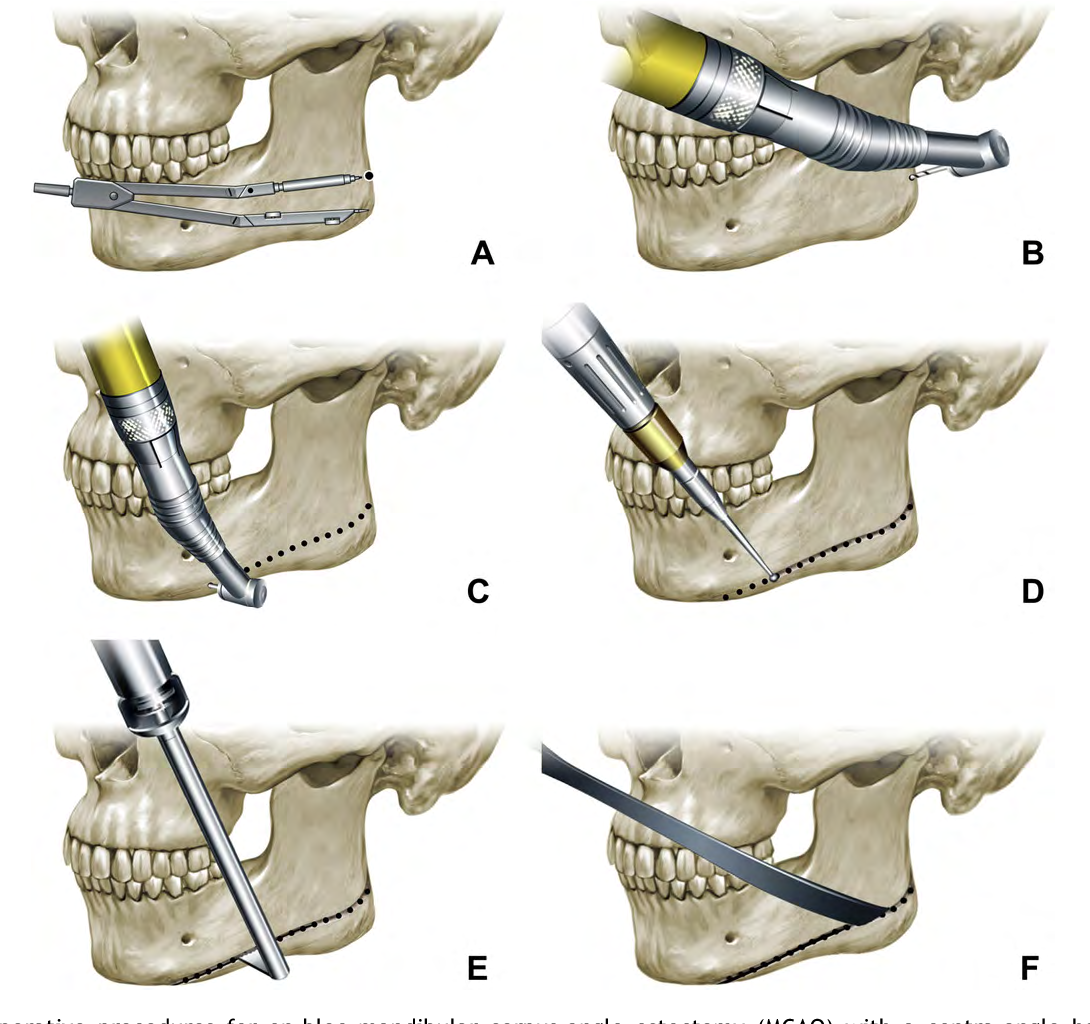

Knowing chin wings can perform such cuts :

Knowing chin wings can perform such cuts :